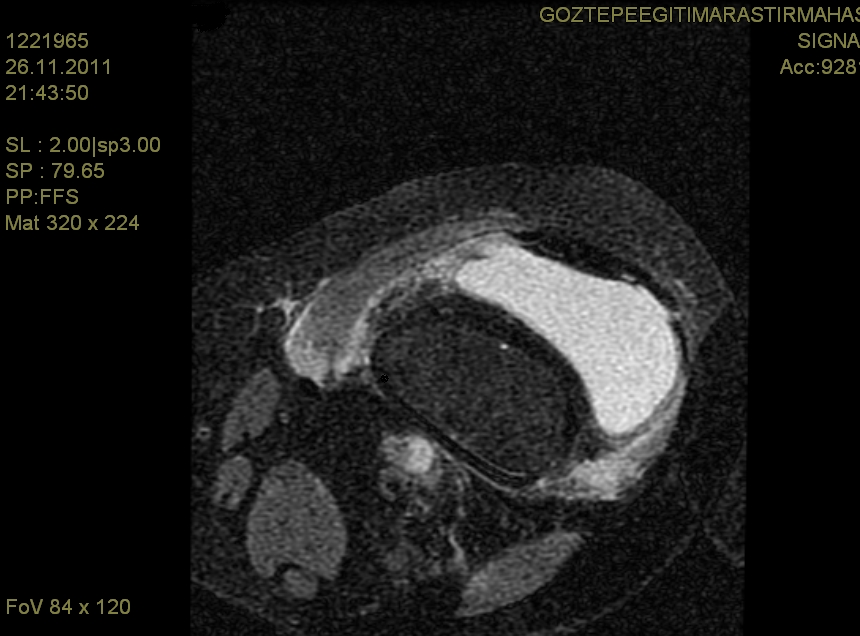

As a Rare Site of Invasive Fungal Infection, Chronic Granulomatous Aspergillus Synovitis: A Case Report